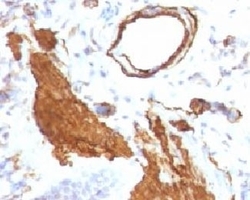

- Genetic validation

- Main image

- Experimental details

- Formalin-fixed, paraffin-embedded rat lung stained with alpha Smooth Muscle Actin antibody (ACTA2/791). This image was taken for the unmodified form of this product. Other forms have not been tested.

- Enhanced method

- Genetic validation

- Main image

- Experimental details

- Formalin-fixed, paraffin-embedded rat lung stained with alpha Smooth Muscle Actin antibody (ACTA2/791). This image was taken for the unmodified form of this product. Other forms have not been tested.

- Genetic validation

- Main image

- Experimental details

- Formalin-fixed, paraffin-embedded rat lung stained with alpha Smooth Muscle Actin antibody (ACTA2/791). This image was taken for the unmodified form of this product. Other forms have not been tested.